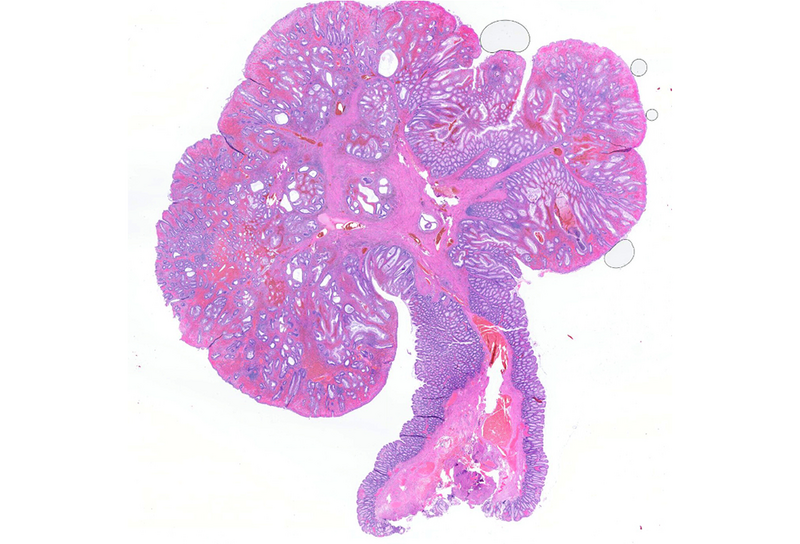

Histologically, the lesion exhibited a complex lobulated architecture (Panel A), with central cores of ramifying bands of smooth muscle extending from the muscularis mucosae into the lamina propria, configuring an arborizing pattern (Panel B). The epithelium exhibited neither cytologic nor architectural atypia and was regarded as reactive (non-dysplastic), with some glands showing dilation and distortion (Panel C). Recovering epithelium was observed on the surface, together with granulation tissue (Panel D).